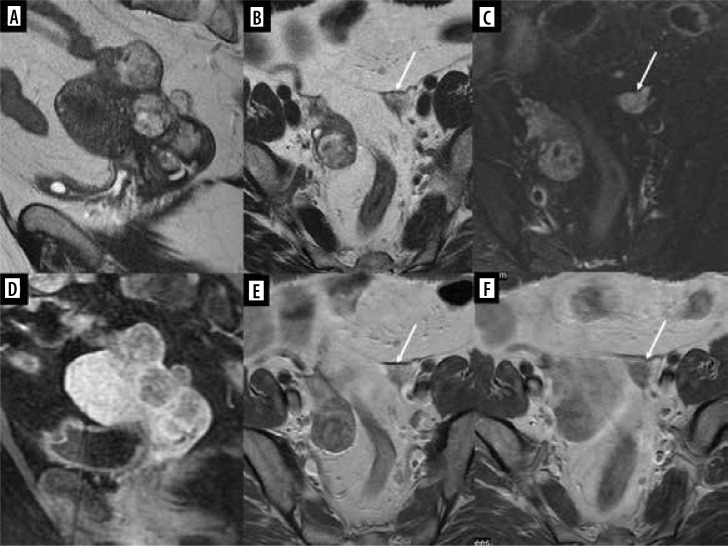

报告了四例软组织或骨肉瘤转移到生殖系统或乳房的女孩病例。其中两名患者的四肢横纹肌肉瘤(RMS)转移至乳房,一名患者的足部横纹肌肉瘤转移至卵巢,一名患者的骶骨软骨肉瘤转移至子宫静脉丛。在每个病例中,转移灶的外观都通过不同的成像方法显示出来:超声波、磁共振成像和计算机断层扫描。全面的文献回顾证实,只有少数病例描述过女孩软组织和骨肉瘤转移到本文主要关注的部位,尤其是生殖器官。尽管这种类型的转移很少发生,但在区分来源时,仍应考虑上述恶性肿瘤。这些罕见的临床情况被编织成一篇关于恶性肿瘤转移到生殖器官和乳房的综述。

Four cases of girls with metastases of soft tissue or bone sarcomas to the reproductive system or breasts are reported. Two patients had metastases to the breast from rhabdomyosarcoma (RMS) of the limbs, one had metastases to the ovary from RMS of the foot, and one had metastases to the uterine venous plexus from chondrosarcoma of the sacrum. In each case, the appearance of metastases was shown in various imaging methods: ultrasound, magnetic resonance imaging, and computed tomography. A thorough literature review confirmed that only a few cases of soft tissue and bone sarcoma metastasis to the locations of primary interest of this article in girls have been described, especially in the context of reproductive organs. Despite the rare occurrence of this type of metastases, the malignant tumours mentioned above should be considered when differentiating the source. These rare clinical situations are woven into a review of malignant neoplasms' metastases to the reproductive organs and breast.